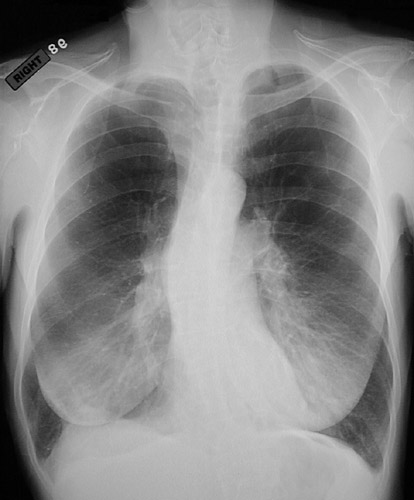

| The PA chest radiograph of this female patient above reveals severe centrilobular emphysema, most marked in upper and mid-lung fields with flattening of the diaphragms. The 10th pair of ribs is easily seen. (The curvature of the vertebral column represents thoracic scoliosis). A lateral view is shown below. |